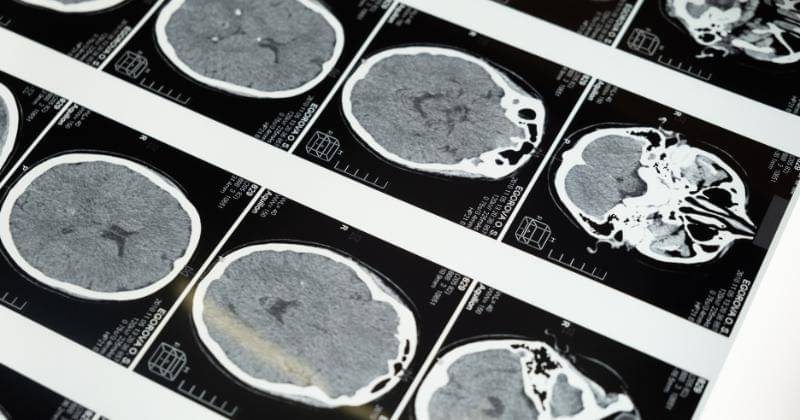

Kabar tidak menyenangkan datang dari pasangan artis, Ruben Onsu dan Sarwendah. Baru-baru ini Ruben mengumumkan ke publik bahwa ia menderita penyakit lesi otak. Di kesempatan yang sama, ia juga mengabarkan bahwa istrinya, Sarwendah, menderita kista di batang otak.

Kista otak atau lesi otak kistik adalah kantung berisi cairan di otak. Mereka bisa jinak (bukan kanker) atau ganas (kanker). Jinak artinya pertumbuhannya tidak menyebar ke bagian tubuh lainnya.

Kista bisa berisi darah, nanah, atau bahan lain. Di otak, kista terkadang mengandung cerebrospinal fluid (CSF). CSF adalah cairan bening yang membasahi dan melindungi otak dan sumsum tulang belakang. Beberapa kista otak sudah terjadi sebelum lahir.